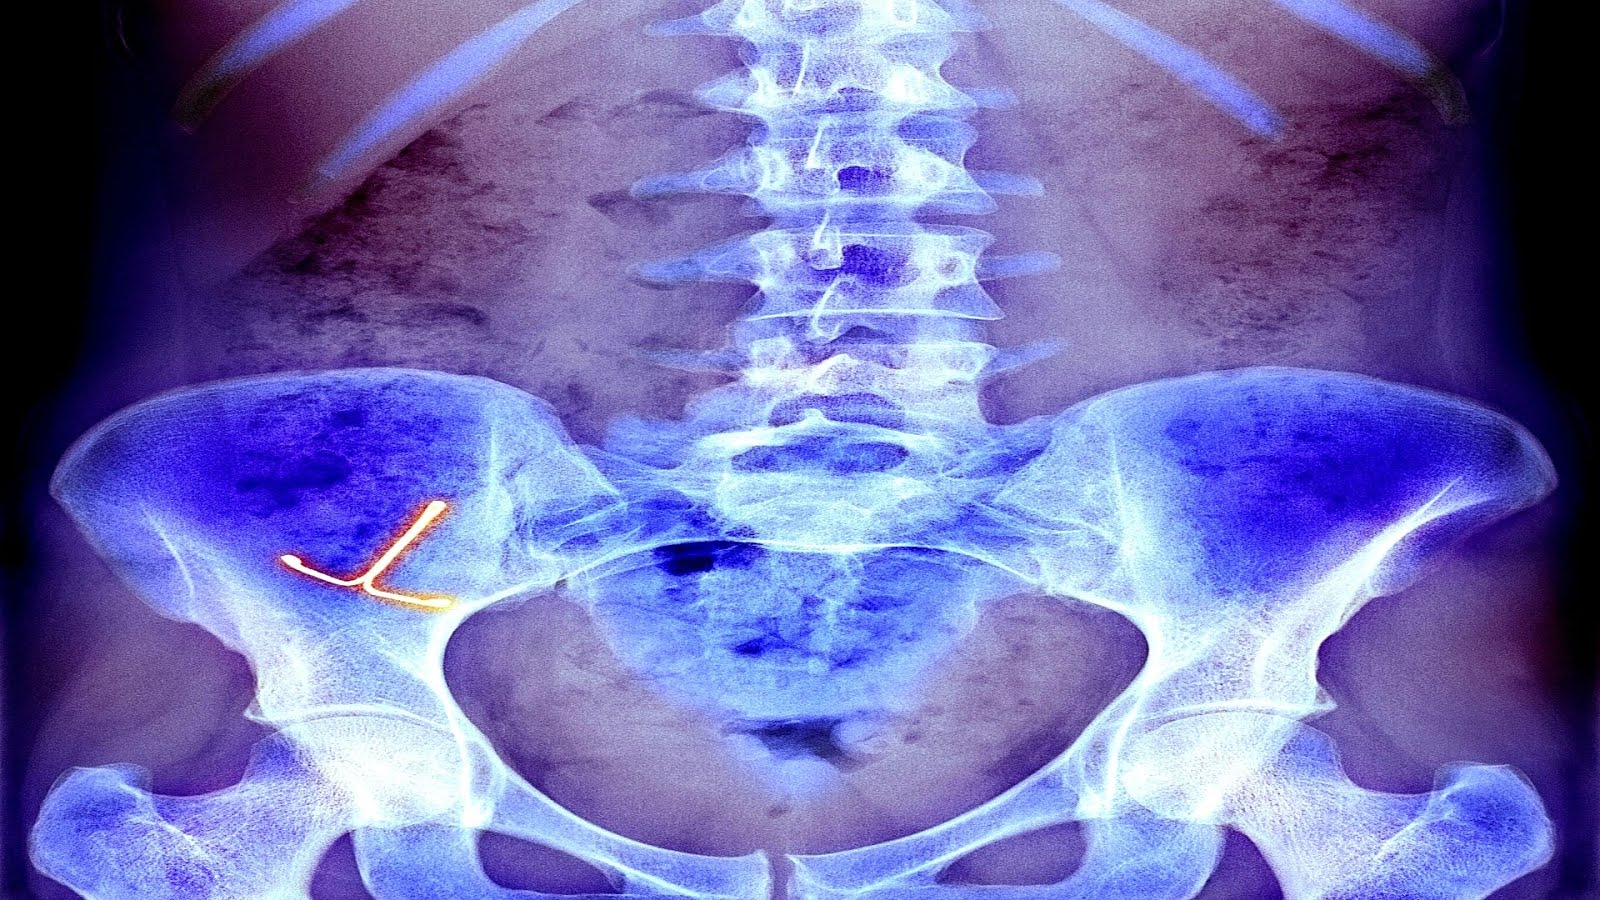

Мужчина чувствует спираль

Мужчина чувствует спираль 113 фотографий